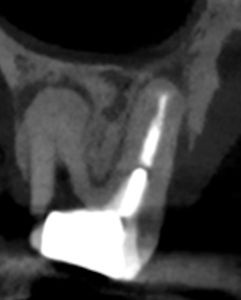

ちなみにPの再根管治療は、

作業長は16.0mm前後が予想される。

まず#3 P Re-RCTから行われた。

#3 P Re-RCT(2025.8.27)

PはC+ Fileで穿通しない。

HyFlex EDM #10.05で機械的に穿通を試みた。

その際の作業長はCBCTから16.0mmである。

K#25で穿通した。

#60.02を試適し、BC sealerとともに根管充填した。

この後、支台築造して同日にMB,DB Apicoectomyへ移行した。

そしてP根だが、根尖病変の治癒とともに口蓋側の骨欠損が大きく回復しているのがわかる。

HyFlex EDM #60.02でわずか数mm形成しただけなのに、ここまで歯槽骨が回復している。